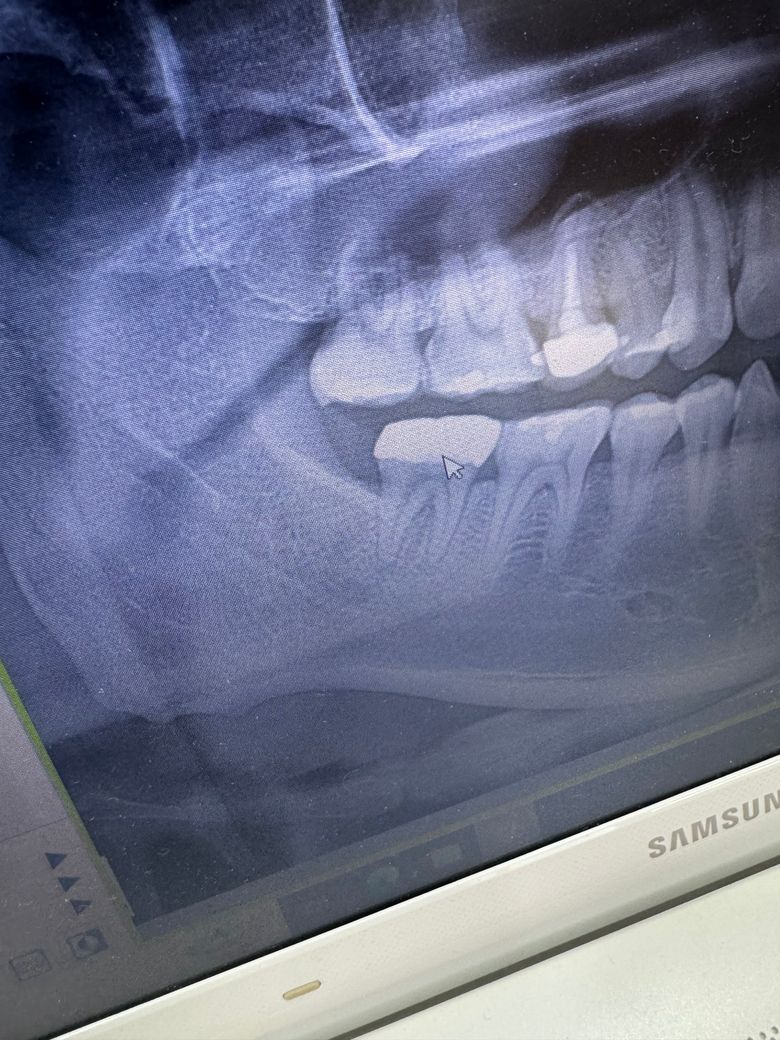

풍치 일까요? 맞다면 발치 유무 가능성 좀 알려주세요

며칠 전 부터 오른쪽 맨 끝 어금니쪽 통증 충치치료1년된 이빨 쪽 통증이 심해서 근처 동네치과를 갔는데 풍치라고 발치를 권유 하네요

사진 상으로 보아서는 잇몸 염증 등으로 인하여 치조골이 많이 소실된 것으로 보여지긴 합니다. 하지만 현재 보여주신 panorama 사진 만으로는 알 수 없으며, 치조골 내의 치아 상태에 대한 정확한 평가를 위해서는 x-ray 및 ct 등을 촬영해 보아야 합니다.

풍치의 가능성은 있어 보이며 발치를 할 정도는 아닌 것 같습니다. 치료 받으면 될 것 같습니다.

일단은 잇몸이 안좋아서 그럴수도 잇으니 잇몸치료를 먼저 받아보시고 치아가 흔들리지 않다면 치료를 해서 사용하시는게 좋을것같습니다.

잇몸뼈가 다소 녹긴했으나 위 엑스레이만 봐서는 발치까지는 좀 더 신중히 생각해보는 것이 좋을 것 같습니다